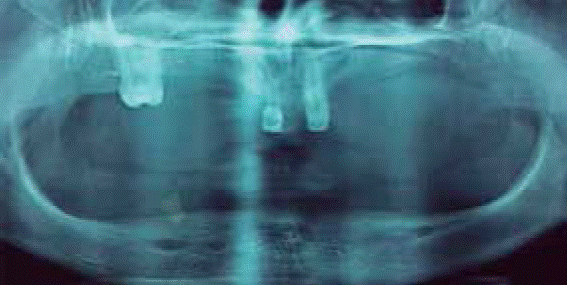

Al examen estomatológico se observa atrofia ósea de los procesos alveolares en ambos maxilares, se destaca anodoncia verdadera de OD # 11, 12 ,13, 14, 15, 16, 18, 22, 23, 24, 25, 26, 27, 28, 31, 32, 33, 34, 35, 36, 37, 38, 41, 42, 43, 44, 45, 46, 47, 48, presencia de órgano dentario deciduo 51 con forma cónica y movilidad, además sobreinserción del frenillo labial superior. Los rebordes alveolares del maxilar superior e inferior se disponen como clase III según la clasificación de Seibert. Se diagnosticó gingivitis marginal leve asociada a placa bacteriana generalizada (Figura 2).

Radiográficamente se observaron colapsos de reborde superior e inferior clase III según la clasificación de Seibert, presencia de un resto radicular a nivel de OD 43 y zonas radiopacas a nivel del 51 compatible con obturación (Figura 3).